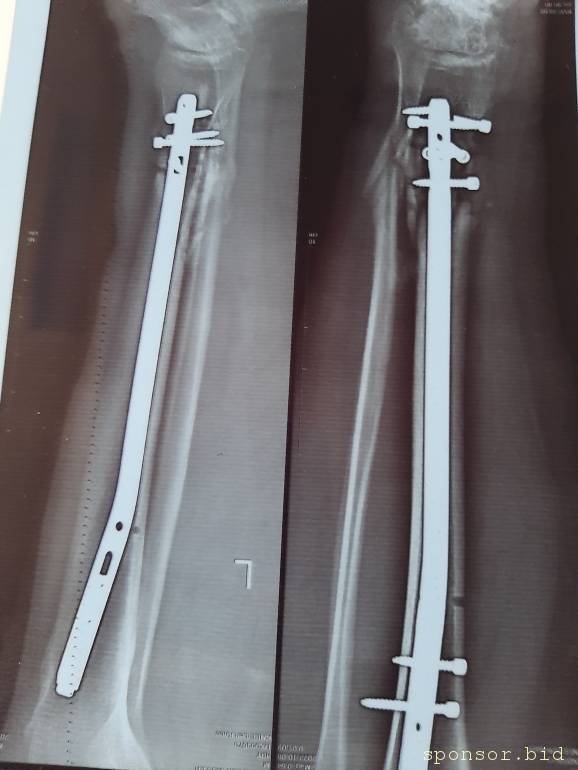

Вот что со мной произошло: летом прошлого 2022 года я неудачно упал, и сломал левую ногу, да так, что всё не закончлось просто гипсом. Перелом был сложным, пришлось делать операцию, ставить биос. Операция прошла с осложнениями, был свищ, нога после операции долго не заживала. Потом сломался крепёжный саморез, стало ещё хуже. Заболела правая нога в колене и бёдре. На приёме у врача сказали нужна операция! И в ближайшее время! Но я на больничном уже целый год, и после такого продолжительного лечения, все мои финансы на нуле. Ходить не могу, спать не могу, мучают постоянные боли. У меня развился сахарный диабет, ноги болят, появилась венозная недостаточность и варикоз. Мне всего 41 год. Получается я останусь инвалидом навсегда... Но у меня есть двое детей 5 и 14 лет... В данный момент я не могу встать на ноги из-за отсутствия финансовых средств. Моя мама Лариса Андреевна, помогает мне по мере своих сил. Ей приходится работать на производстве. Но ей уже 75 лет...

Нужна помощь сыну сотрудницы Не может ходить. - 20230719_135256.jpg

Нужна помощь сыну сотрудницы Не может ходить. - 20230719_135335.jpg